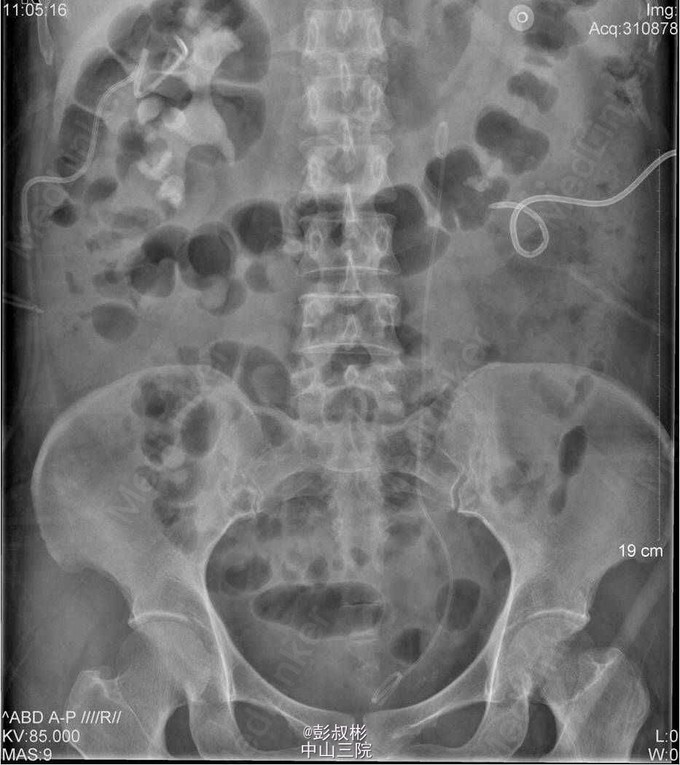

1、因“反复下腰部胀痛伴发热2月,加重10天” 入院。入院前最高体温39.5℃ ,外院检查尿隐血及尿白细胞3+,进一步行泌尿系B超显示双肾及左输尿管下段结石,左肾重度积液 。 2、既往史: 10年前因肾结石行体外冲击波碎石术,自诉术后恢复良好。 3、辅助检查:1) 血常规(抗炎后)、血生化(补钾后)、肝功、凝血、术前八项、胸片及心电图未见明显异常; 2) 尿常规:12.9 :尿液白细胞+++ 尿液红细胞++ 左肾造瘘液白细胞++ 左肾造瘘液红细胞++ 3) 真菌培养:无真菌生长 4) 肾功能:12.9: 肌酐5.68 mmol/L尿素氮: 186 nmol/L 5) 核素肾动态显像+GFR双血浆测定 1.右肾灌注、功能中度受损,右上尿路慢性梗阻。 2.左肾灌注、功能中度受损,左上尿路机械性梗阻。 灌注相:双肾于腹主动脉显影后2秒开始显影,放射性灌注明显减低(右肾明显低于左肾)。灌注曲线分析:双肾灌注峰明显减低。 功能相:右肾影稍增大,放射性摄取明显减低,放射性分布不均匀,可见多发放射性分布稀疏缺损区,放射性排泄缓慢。左肾增大,放射性摄取减低,放射性分布不均匀,可见多发放射性分布稀疏缺损区,放射性排泄缓慢,左肾盏见明显放射性滞留。半小时内膀胱可见放射性积聚。 肾图:右肾a段降低,b、c段融合为低水平延长型肾图。左肾a段降低,b、c段融合为持续上升型肾图。双血浆法肾小球滤过率(GFR)左肾为19.7ml/min,右肾GFR为17.9ml/min。 6) 双肾CTU平扫+增强螺旋扫描 1、左肾多发结石、重度积液、肾功能减退,左输尿管膀胱入口处结石,左侧输尿管炎症; 2、右肾多发结石、轻度积液,右肾功能减退,右肾盂及输尿管炎症。 4、诊断:双肾积脓 右肾铸形结石 左肾多发结石 左输尿管下段结石碎石术后 双肾功能减退 5、入院后处理:予以“舒普深” 3.0 Bid 抗感染,12-5 行“B超引导下经皮左肾穿刺造瘘术”,每日引流出约1500ml脓液。肾功能改善后于12-9行“左侧输尿管镜下钬激光碎石取石术”,术程顺利,术后予以舒普深3.0 Bid抗感染,体温正常。昨日下午行“B超引导下经皮右肾穿刺造瘘术”。